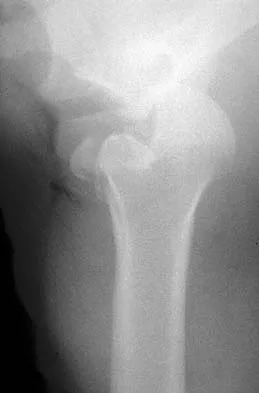

A 21-year-old patient has had pain and a marked decrease in active and passive shoulder motion after having had a seizure 2 months ago as the result of alcohol abuse. Current AP and axillary radiographs and a CT scan are shown in Figures 26a through 26c. Management should consist of

Open reduction and subscapularis and lesser tuberosity transfer into the defect is the treatment of choice in young individuals who have defects that involve between 20% to 45% of the head. Disimpaction and bone grafting is an option in injuries that are less than 3 weeks old. Closed reduction 2 to 3 months after injury usually is unsuccessful and increases the risk of fracture or neurovascular injury. Total shoulder arthroplasty is reserved for defects of greater than 50% or with associated glenoid surface damage. Hemiarthroplasty should be avoided in young individuals unless 50% or more of the head is involved. Gerber C: Chronic locked anterior and posterior dislocations, in Warner JJ, Iannotti JP, Gerber C (eds): Complex and Revision Problems in Shoulder Surgery. Philadelphia, PA, Lippincott-Raven, 1997, pp 99-113.